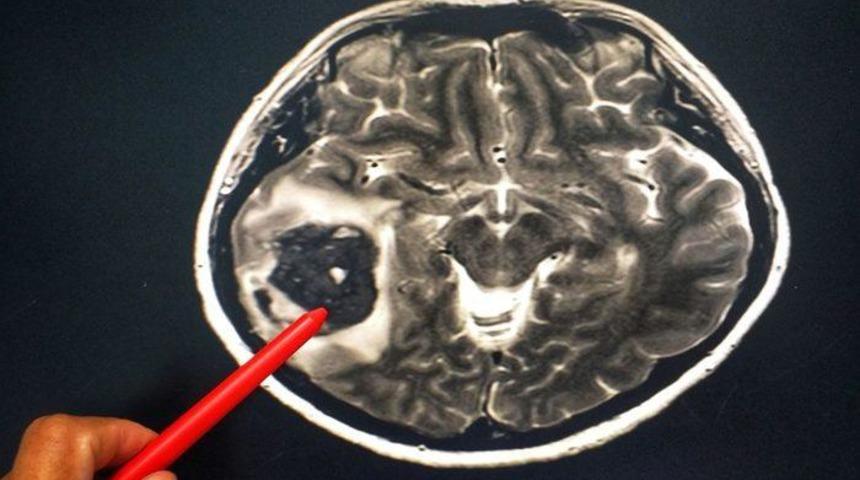

Gribin, zatürre ve beyin iltihabına yol açabildiğini belirten uzmanlar, bu enfeksiyonun, dünyada okula ya da işe devamsızlığın yüzde 10'undan sorumlu tutulduğunu belirtti. Halk arasında sıklıkla nezleyle karıştırılan grip, çok bulaşıcı, mutlaka yatarak istirahati gerektiren, bazen ölüme bile neden olabilen ciddi bir sağlık sorunu olarak kabul ediliyor.

"Boğaz ağrısı için gargara, pastiller kullanılabiliyor. Çocuklarda aşırı sıvı salınımına bağlı silier fonksiyon kaybını önlemek için bol sıvı alımı gerekir. Burun tıkanıklığını gidermek için burun damlaları kullanılabilir. Grip viral bir hastalık olduğu için bakteri enfeksiyonlarında kullanılan antibiyotiğin yararı yoktur. Sağlıklı bireylerde grip, 1 hafta 10 için içinde kendiliğinden iyileşir. Grip özellikle risk grubundaki hastalarda bronşit, zatürre gibi hastalıklar nedeniyle ölüme yol açabilir."